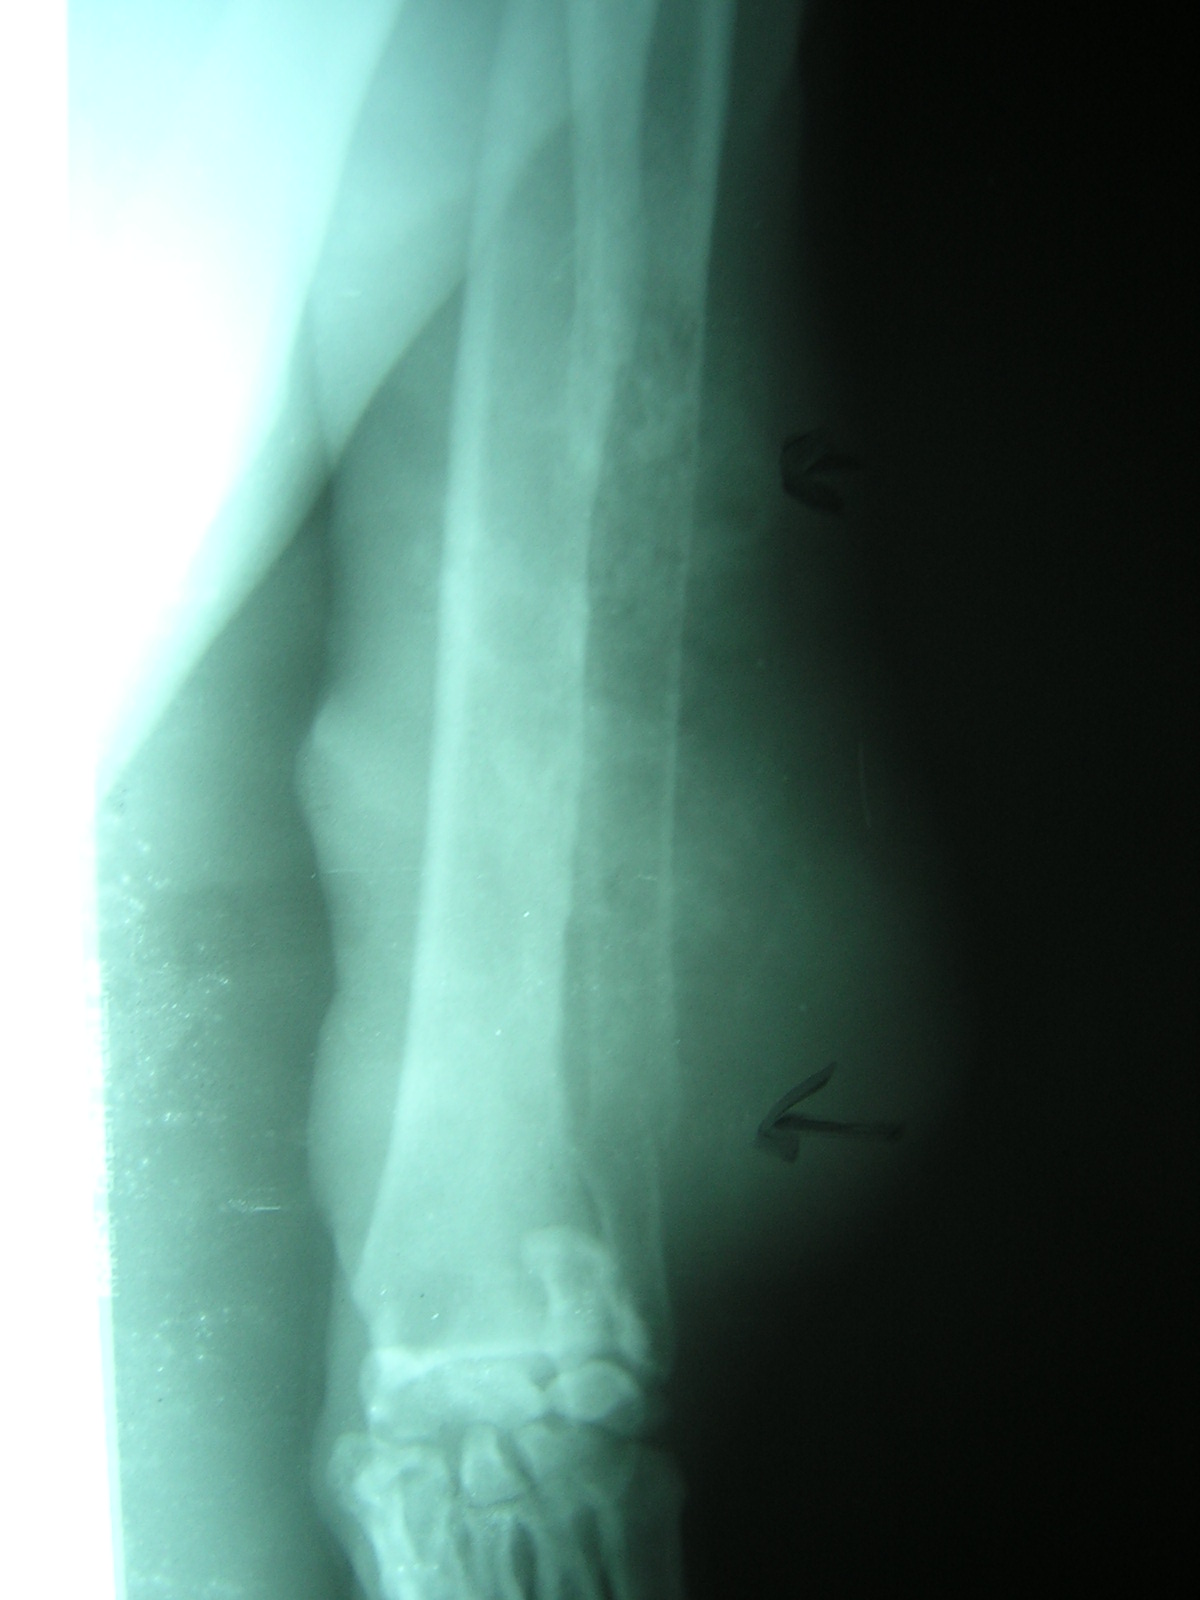

Las lesiones neoplásicas en huesos de pequeños animales no son ajenas a nuestra práctica diaria.